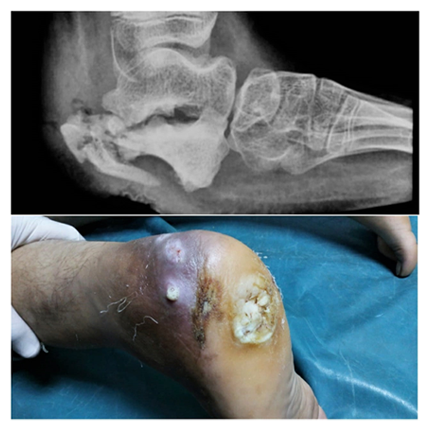

Case - 3

Before

Figure showing X ray and clinical image of Chronic osteomyelitis left heal with non healing ulcer post meningomyelocoele

After

6 month follow up images showing complete healing